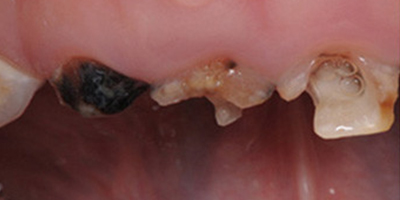

效果對(duì)比圖

顯微鏡根管治療術(shù)前